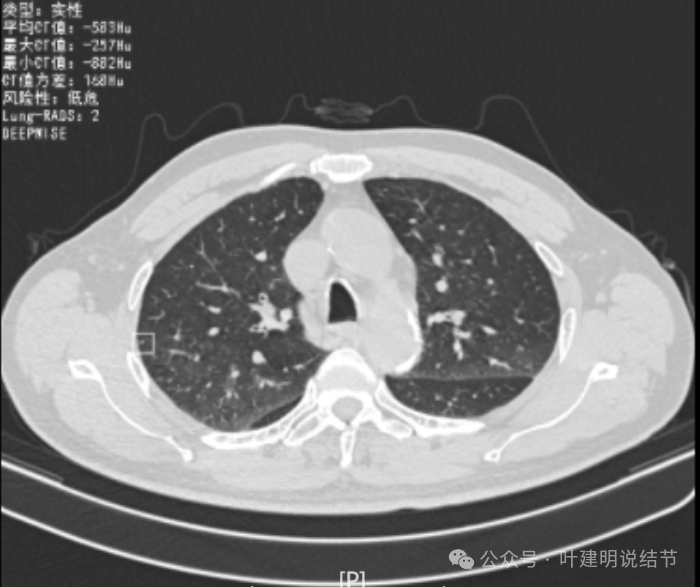

我们先来看2022年3月主要病灶的影像:

右上叶结节实性,密度高,边缘平整,轮廓清楚,像良性些。

右下似见微小结节,实性,与边上小血管截面不太好区分,过小没什么临床意义,能随访。

左下胸膜下实性结节,轮廓稍模糊,密度较高,边缘较光,像淋巴结些,能随访。

再看2022年8月复查时AI报告找出来的影像:

多是微小实性结节,主要的仍是右上与左下的这两处,较3月时无明显变化。而右下原来似有微小结节处这次并不明显。